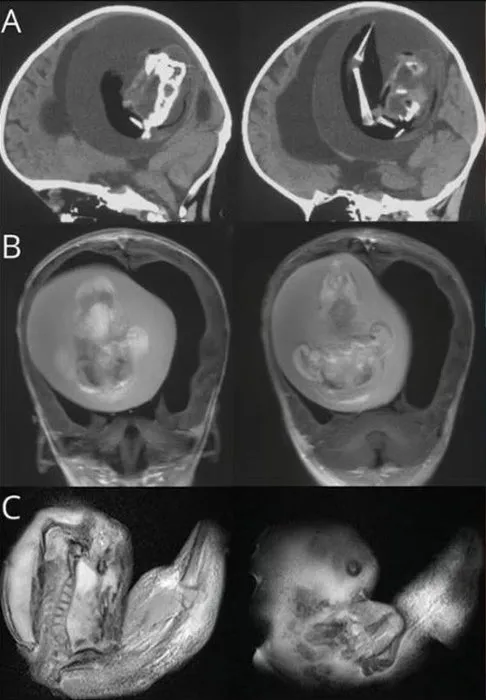

Çin'de bir yaşındaki bebeğin beyninden ikizinin fetüsü çıkarıldı. Bunun tarihte yalnızca birkaç kez yaşanan bir anomali olduğunu dile getiren uzmanlar, bebeğin kafatasının beklenenden daha geniş olması nedeniyle durumun fark edildiğini belirtti.

Tıp literatüründe yalnızca birkaç kez ortaya çıkan ilginç bir olay yaşandı. Çin'de bir yaşındadaki bir bebeğin kafatasının beklenenden geniş olduğu ve motor becerilerinde sorunlar görüldüğü gerekçesi ile hastaneye kaldırılmıştı. Bebeği hastalığı şaşkına çevirdi.

Emekleme, ayakta durma, yürüme, koşma, salınım, dönme, yuvarlanma, zıplama ve denge kurma gibi hareketlerin gerçekleştirilmesini sağlayan motor becerilerini gerçekleştiremeyen bebeğin kafatasında ikiz kardeşi olduğu tespit edildi.

Bebeğin beyninin sıkıştığı ve içinde sıvı birikimi olduğu tepsit edilinceileri incelemeler yapıldı.

Buna benzer bir olay İngiltere'de 1982'de Londra Hastanesi'ndeki bilim insanları tarafından bulunmuştu.